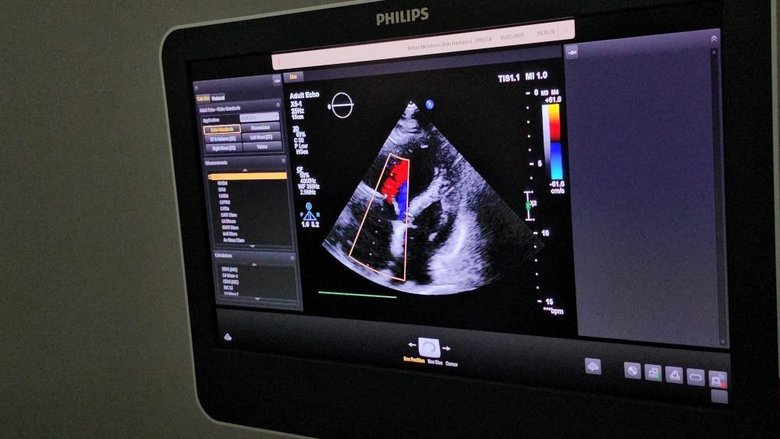

Hastanın durumu hakkında bilgi veren Dr. Öğr. Üyesi Sevil Gülaştı, daha önce kifoplasti-vertebroplasti işlemi geçiren hastanın kullanılan dolgu maddesinin (sement) damarlara sızarak pulmoner emboliye neden olduğunu ve bunun hayati risk taşıyan ciddi bir durum oluşturduğunu belirtti. Gülaştı, "Hastamız tekrarlayan nefes darlığı şikâyetiyle sık sık acil servise başvuruyordu. Yapılan tetkiklerde vertebroplastide kullanılan polimetilmetakrilat maddesinin toplardamarlara sızarak kalbe kadar ulaştığını tespit ettik. Bu durumun tekrarlayan pulmoner embolilere neden olması üzerine hastayı multidisipliner bir yaklaşımla değerlendirdik" dedi.

İlk aşamada cerrahi yöntem düşünülse de, hastanın yüksek risk taşıması nedeniyle özel olarak modifiye edilen bir kateter ile sağ boyun toplardamarından girilerek yabancı cismin kapalı yöntemle çıkarılmasına karar verildiğini ifade eden Doç.Dr. Cemil Zencir, "Hastamızın durumu birçok branşla değerlendirildi. Bu tür girişimlerde hastanın güvenliği önceliklidir. Sementin mukavemet gücünü değerlendirdikten sonra uygun yöntemi belirledik ve kapalı bir teknikle tek parça halinde çıkardık. Bu önemli girişim, bilindiği kadarıyla Türkiye'de ilk kez Üniversitemiz Hastanesinde başarıyla gerçekleştirildi. Hasta, Üniversitemiz Hastanesindeki hızlı ve etkili müdahale ile sağlığına kavuşurken, bu yenilikçi yöntem tıbbi gelişmelere önemli bir katkı sundu" dedi.